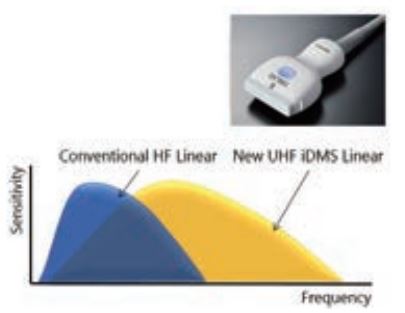

Однак найвидатнішою новою розробкою є надвисокочастотний датчик, який працює на частотах до 24 МГц, що раніше було неможливо уявити в клінічній візуалізації. Цей новий датчик забезпечує відмінну просторову роздільну здатність як для зображень у відтінках сірого, так і

для доплерівських зображень, але при цьому має цілком достатню глибину проникнення, що дозволяє використовувати його в звичайних клінічних дослідженнях. Підвищений діапазон частот розширює горизонти клінічного ультразвуку, дозволяючи відображати анатомію і досліджувати

структури, які раніше були недоступними.

Мал. 2. Надвисокочастотний лінійний датчик